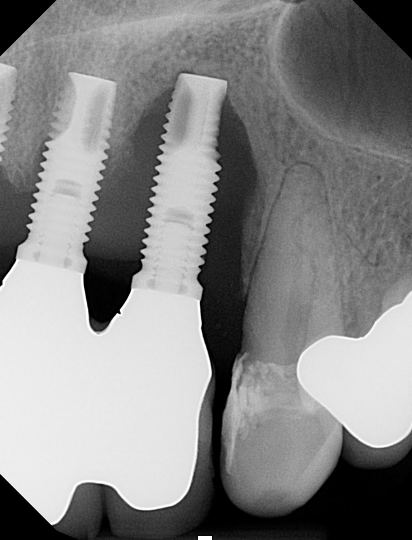

(1.) Peri-implantitis bone loss.

Figure 1

(2.) Peri-implantitis bone loss.

Figure 2

Peri-implantitis is defined as a bacterial plaque-associated pathological condition related to oral biofilm occurring in tissues around dental implants, characterized by inflammation in the peri-implant mucosa and subsequent progressive loss of surrounding bone1-8(Figure 1 and Figure 2). Food impaction is a contributing but not a primary factor in the disease process.